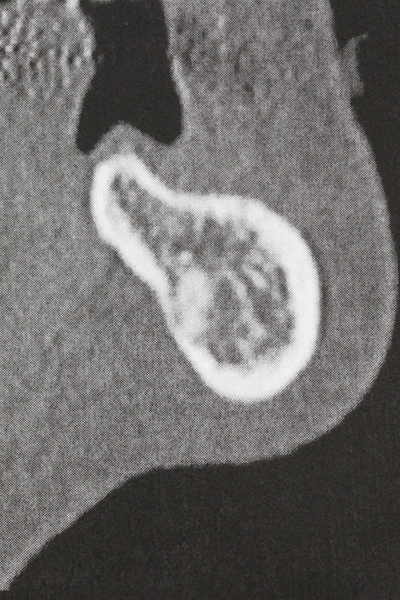

Indication: Bone splitting

Bone tissue is not simply a mineral structure but also contains a substantial proportion of collagen fibres. This means it not only has good compressive strength but also a degree of flexibility, which can be taken advantage of when performing bone augmentations. In the classical expansion procedure using bone splitting, the atrophied alveolar ridge is split longitudinally and carefully expanded after reaching an adequate osteotomy depth (Fig. 13-16), ideally without substantial removal of the periosteum (Brugnami, Caiazzo et al. 2014, Stricker, Fleiner et al. 2014). Screw and plate systems with increasing expansion distance have proven effective in separating the two bone lamellae while remaining below the fracture threshold. In general, residual bone widths of at least 3–4 mm are required (Chiapasco, Zaniboni et al. 2006) to guarantee adequate flexibility and sufficient bone coverage of the future implants. If necessary, a vertical relief osteotomy on one or both sides can improve flexibility. A combination with additional augmentation techniques, particularly on the buccal side, has been described as an alternative to the classical technique.

The splitting procedure is particularly atraumatic and there is no significant loss of dimension when using piezosaws, and there are no significant differences between implants in split jaws and implants in an alveolar ridge without a bone deficit (Chiapasco, Zaniboni et al. 2006, Danza, Guidi et al. 2009). However, sufficient continuous irrigation is essential, particularly with locally restricted and deep splitting to prevent thermal stress in the apical osteotomy regions.